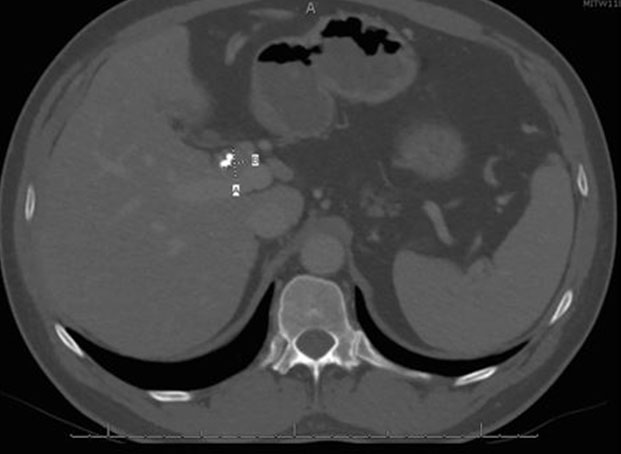

He was discharged from the hospital and seen in surgery clinic, where a bile duct resection, left liver lobe resection, and Roux-en-Y hepaticojejunostomy for possible cholangiocarcinoma were recommended. At this point, he reported that his initial symptoms had improved since his ERCP. His physical exam was normal and his liver chemistry tests revealed mild transaminitis. Total protein and albumin were normal. A computed tomography (CT) abdomen with contrast demonstrated a mass-like thickening of the CHD wall near the right and left hepatic duct bifurcation measuring 13 mm by 17 mm (Figure 2). He also had bilateral hydronephrosis, worse on the right, with abnormal mass-like thickening of the urothelia and retroperitoneal fibrosis on the CT (Figure 3). Given this finding, the differential diagnosis included consideration of IgG4 cholangiopathy, however measured IgG4 was normal at 42.4 mg/dL. A week later, he underwent another ERCP for continued imaging abnormalities and to reobtain tissue to rule out malignancy, which showed mild but improved structuring from the CHD to the hilum and redemonstrated the hilar mass. Samples of the mass for cytology and fluorescence in situ hybridization (FISH) were taken, and the stents were replaced.

Figure 2: CT image showing a 17 mm by 13 mm (dotted lines A and B, respectively) CHD mass. Plastic biliary stents are visualized lateral to the mass. CHD: common hepatic duct; CT: computed tomography.